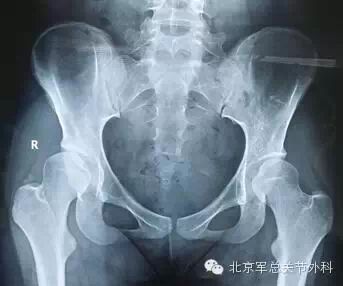

17岁的女孩,右髋疼痛1年加重1月,屈髋疼痛受限。X线检查显示双侧髋关节发育不良,对于这样的病人,是继续保守、等待还是积极手术保髋治疗呢?

X线片显示右髋臼顶关节面硬化,臼顶倾斜角右侧22.8°/左侧19.8°,CE角右侧8.7°/左侧19°,前CE角右侧12°/左侧35.8°。右侧股骨头覆盖明显减小。